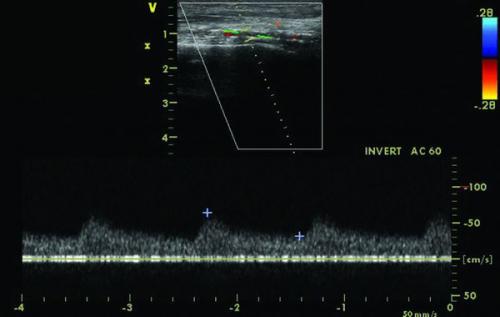

Ультразвуковое дуплексное сканирование (УЗДС) — метод диагностики первой линии. Он позволяет оценить анатомию поражения, движение крови по сосудам и морфологию, а также проверить результаты лечения. Для определения характера поражения используется измерение степени стеноза и критерии качественного и количественного анализа спектра кровотока.

При значимом стенозе увеличивается систолическая скорость кровотока и изменяется контур спектра. В стороне от стеноза регистрируется магистрально изменённый кровоток: в 75-90 % случаев он приобретает коллатеральный тип.